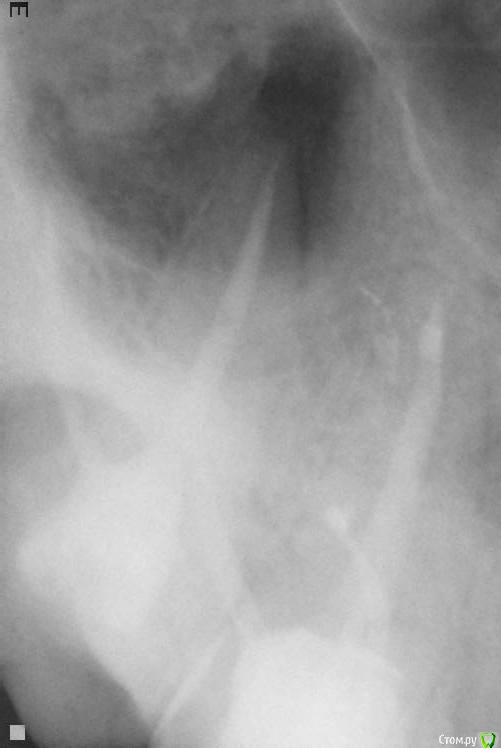

bozz903 Опубликовано 19 марта, 2016 Автор Поделиться Опубликовано 19 марта, 2016 Здравствуйте. С наступлением весны все тот же 16 зуб стал реагировать на температуру очень сильно. Также ноет сам по себе периодически. Боль не похожа на гиперчувствительность эмали.Сделал новые снимки. Что нибудь можно сказать по сравнение с теми, которые прикреплены в первом моем сообщении? Ссылка на комментарий

DmitrySH Опубликовано 19 марта, 2016 Поделиться Опубликовано 19 марта, 2016 (изменено) Низкая информативность снимков. Даже на ОПТГ качество лучше Изменено 19 марта, 2016 пользователем DmitrySH Ссылка на комментарий